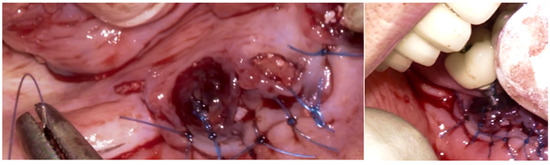

Then, the BSF was reflected to the lingual side (Figure 10c,d), exposing the surgical and infected site. Significant calculus deposits and plaque were noted on and around the implant surfaces. Then, with the screwed pin (hinge) in position, the implantoplasty was performed through the Quadrant protocol using the novel iMPACT device to renew the implant surface, transform it into a machined surface, and contour the surrounding bone (Figure 11).

After completely smoothing the surface of the implants, guided bone regeneration (GBR) was applied (Figure 12); the grafting approach used a combination of 30% Raptos® allograft (cancellous and cortical bone) (Citagenix, Laval, QC, Canada) and 70% bovine xenograft (Bio-Oss, Geistlich, Wolhusen, Switzerland) to maximize structural stability and bioactivity. The grafting material was inserted after being hydrated and condensed into the defect site. A resorbable collagen membrane (Bio-Gide, Geistlich, Wolhusen, Switzerland) covered the graft after it was positioned at the site. The site was sutured with Polyamide 4/0 (Ethicon Ethilon Nylon Suture, Raritan, Raritan, NJ, USA) at 1 mm intervals to ensure wound stability and optimal healing (Figure 13). After being cleansed, the prosthesis was adapted to fit the new gingival line, which changed due to the bone augmentation and suturing of the surgical site.

Figure 10. (a) BSF incision; (b) BSF raised; (c) BSF moved from buccal to lingual; (d) BSF raised exposing the implants and local bone.